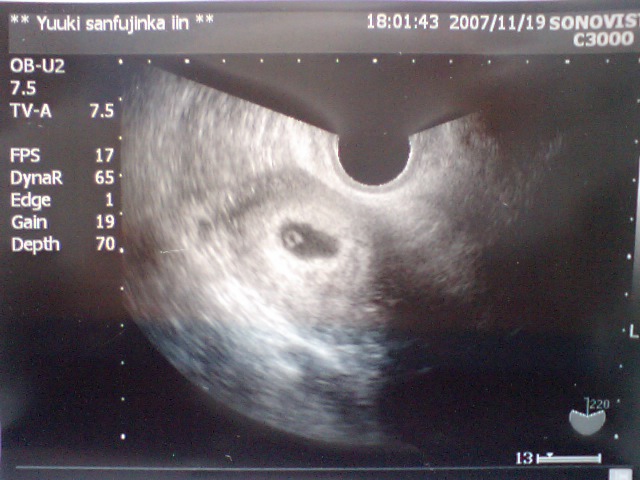

とかいいつつ一応エコー検査をしてもらう。

結果やっぱりまだ何も写っておらず・・・・・。

妊娠判定は出ているが、早すぎてまだ何も見えないのか

子宮外妊娠しているのか、、、

数日後に生理が来て(自然流産)しまうこともあると。

二週間ほど様子を見てから再来することに。